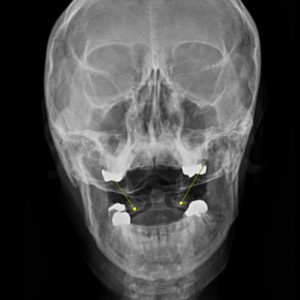

안면 두개골 엑스레이 검사

Submento Vertex View 포함

안면 균형검사

턱의 다양한 각도 사진 촬영

부정교합검사

1,2,3단계 부정교합 유무 파악